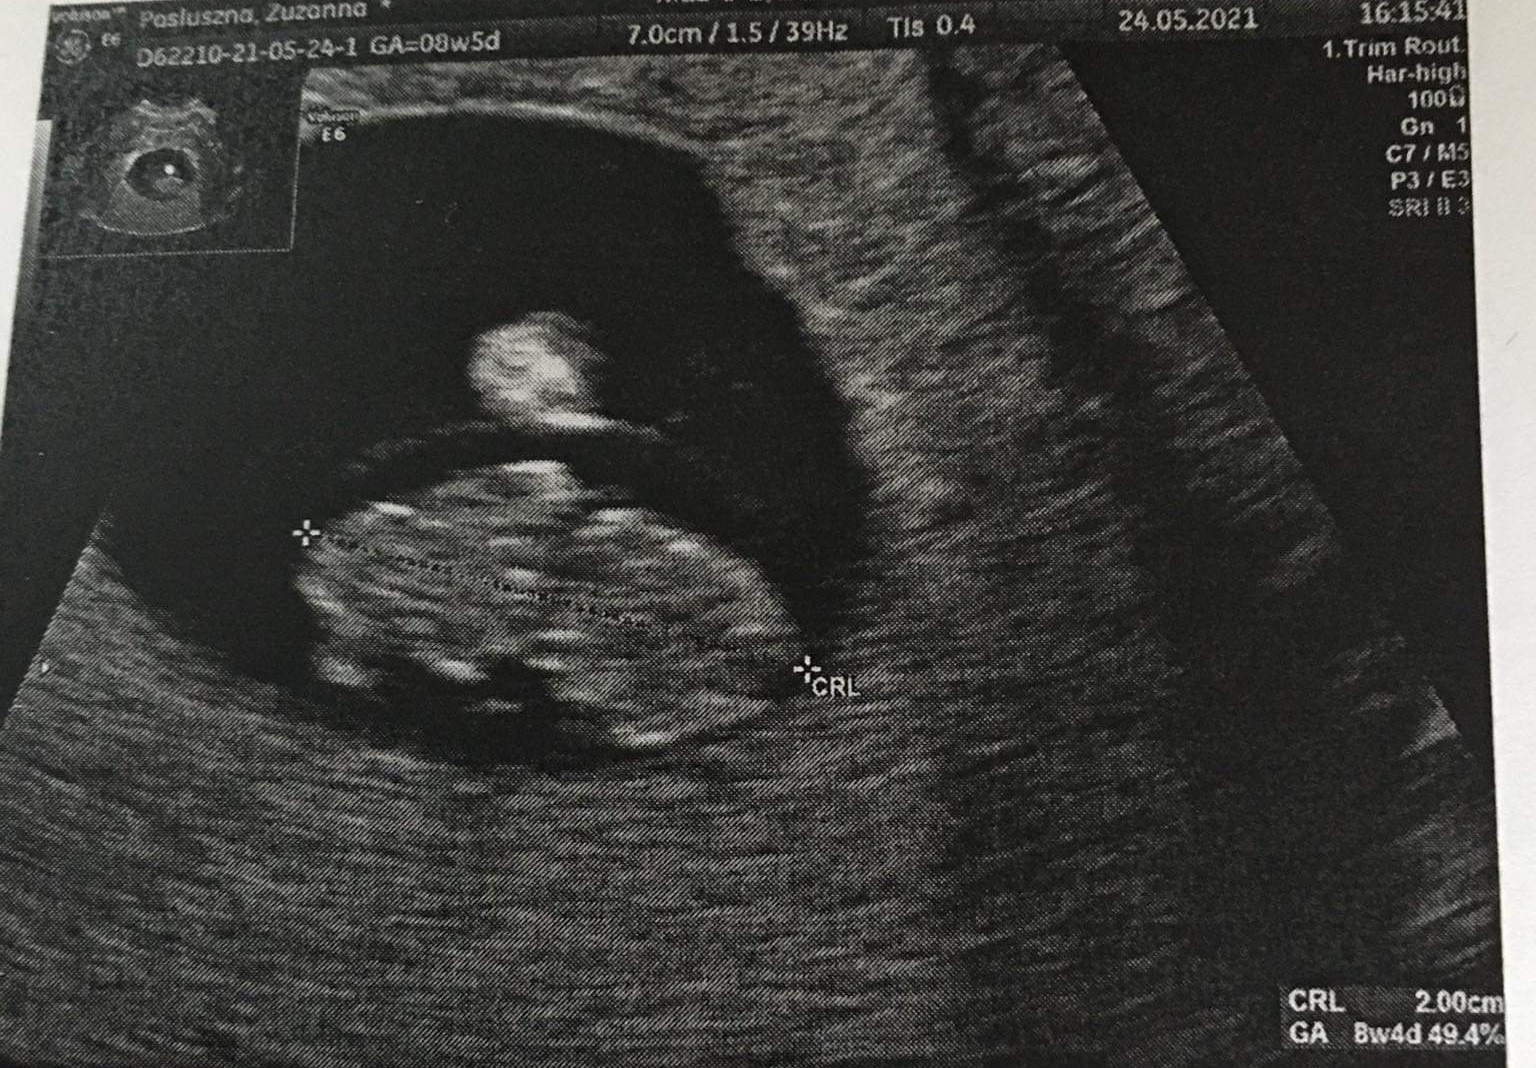

Ja już po wizycie. Wszystko jest w porządku. No cóż jest tak jak myślałam. Ginekolog nie jest zadowolony z leku, który przyjmuje. Jeszcze nigdy nie prowadził takiej ciąży... za 2 tygodnie kolejna wizyta

Załączniki

• 5287956A-7571-4F21-8B39-710EDBC6F7AC.jpeg

5287956A-7571-4F21-8B39-710EDBC6F7AC.jpeg

936,7 KB · Wyświetleń: 133